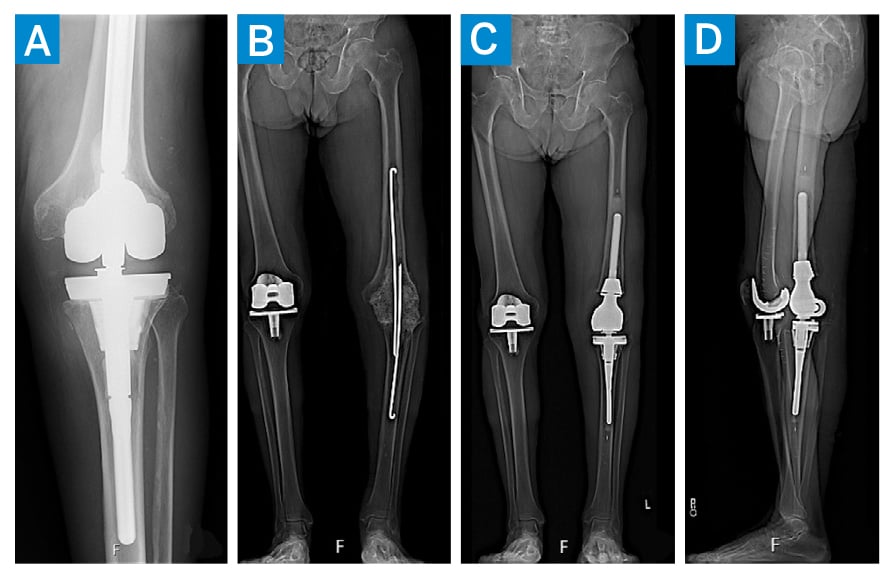

An 86-year-old man with a history of bilateral total knee arthroplasty (TKA) and left revision TKA 3 years later due to aseptic loosening presented to HSS 2 years after that with knee instability and recurrent effusions. A revision to a hinged knee prosthesis was performed; 4 months later, the patient noted knee swelling, with fevers and chills, and was diagnosed with a Staphylococcus schleiferi periprosthetic joint infection (PJI). An incision and drainage with liner exchange was performed, and chronic antibiotic treatment commenced. After a breakthrough PJI after 3 years, he underwent 2-stage exchange with explantation and spacer insertion, followed by reimplantation 2 months later with distal femoral replacement (DFR) (Figure 1).

Figure 1: Radiographs of the left knee after re-revision TKA (A), after explantation and cement spacer insertion (B), and after reimplantation with distal femoral prosthesis (C, D).